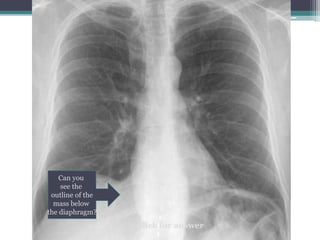

Click for answer

Can you

see the

outline of the

mass below

the diaphragm?

Thoracoabdominal sign

โ€ข Answer: Margin of mass is apparent and below

diaphragm, therefore this must be in the middle or

posterior compartments where it is surrounded by

lung

โ€ข This example is a โ€˜Lipomaโ€™